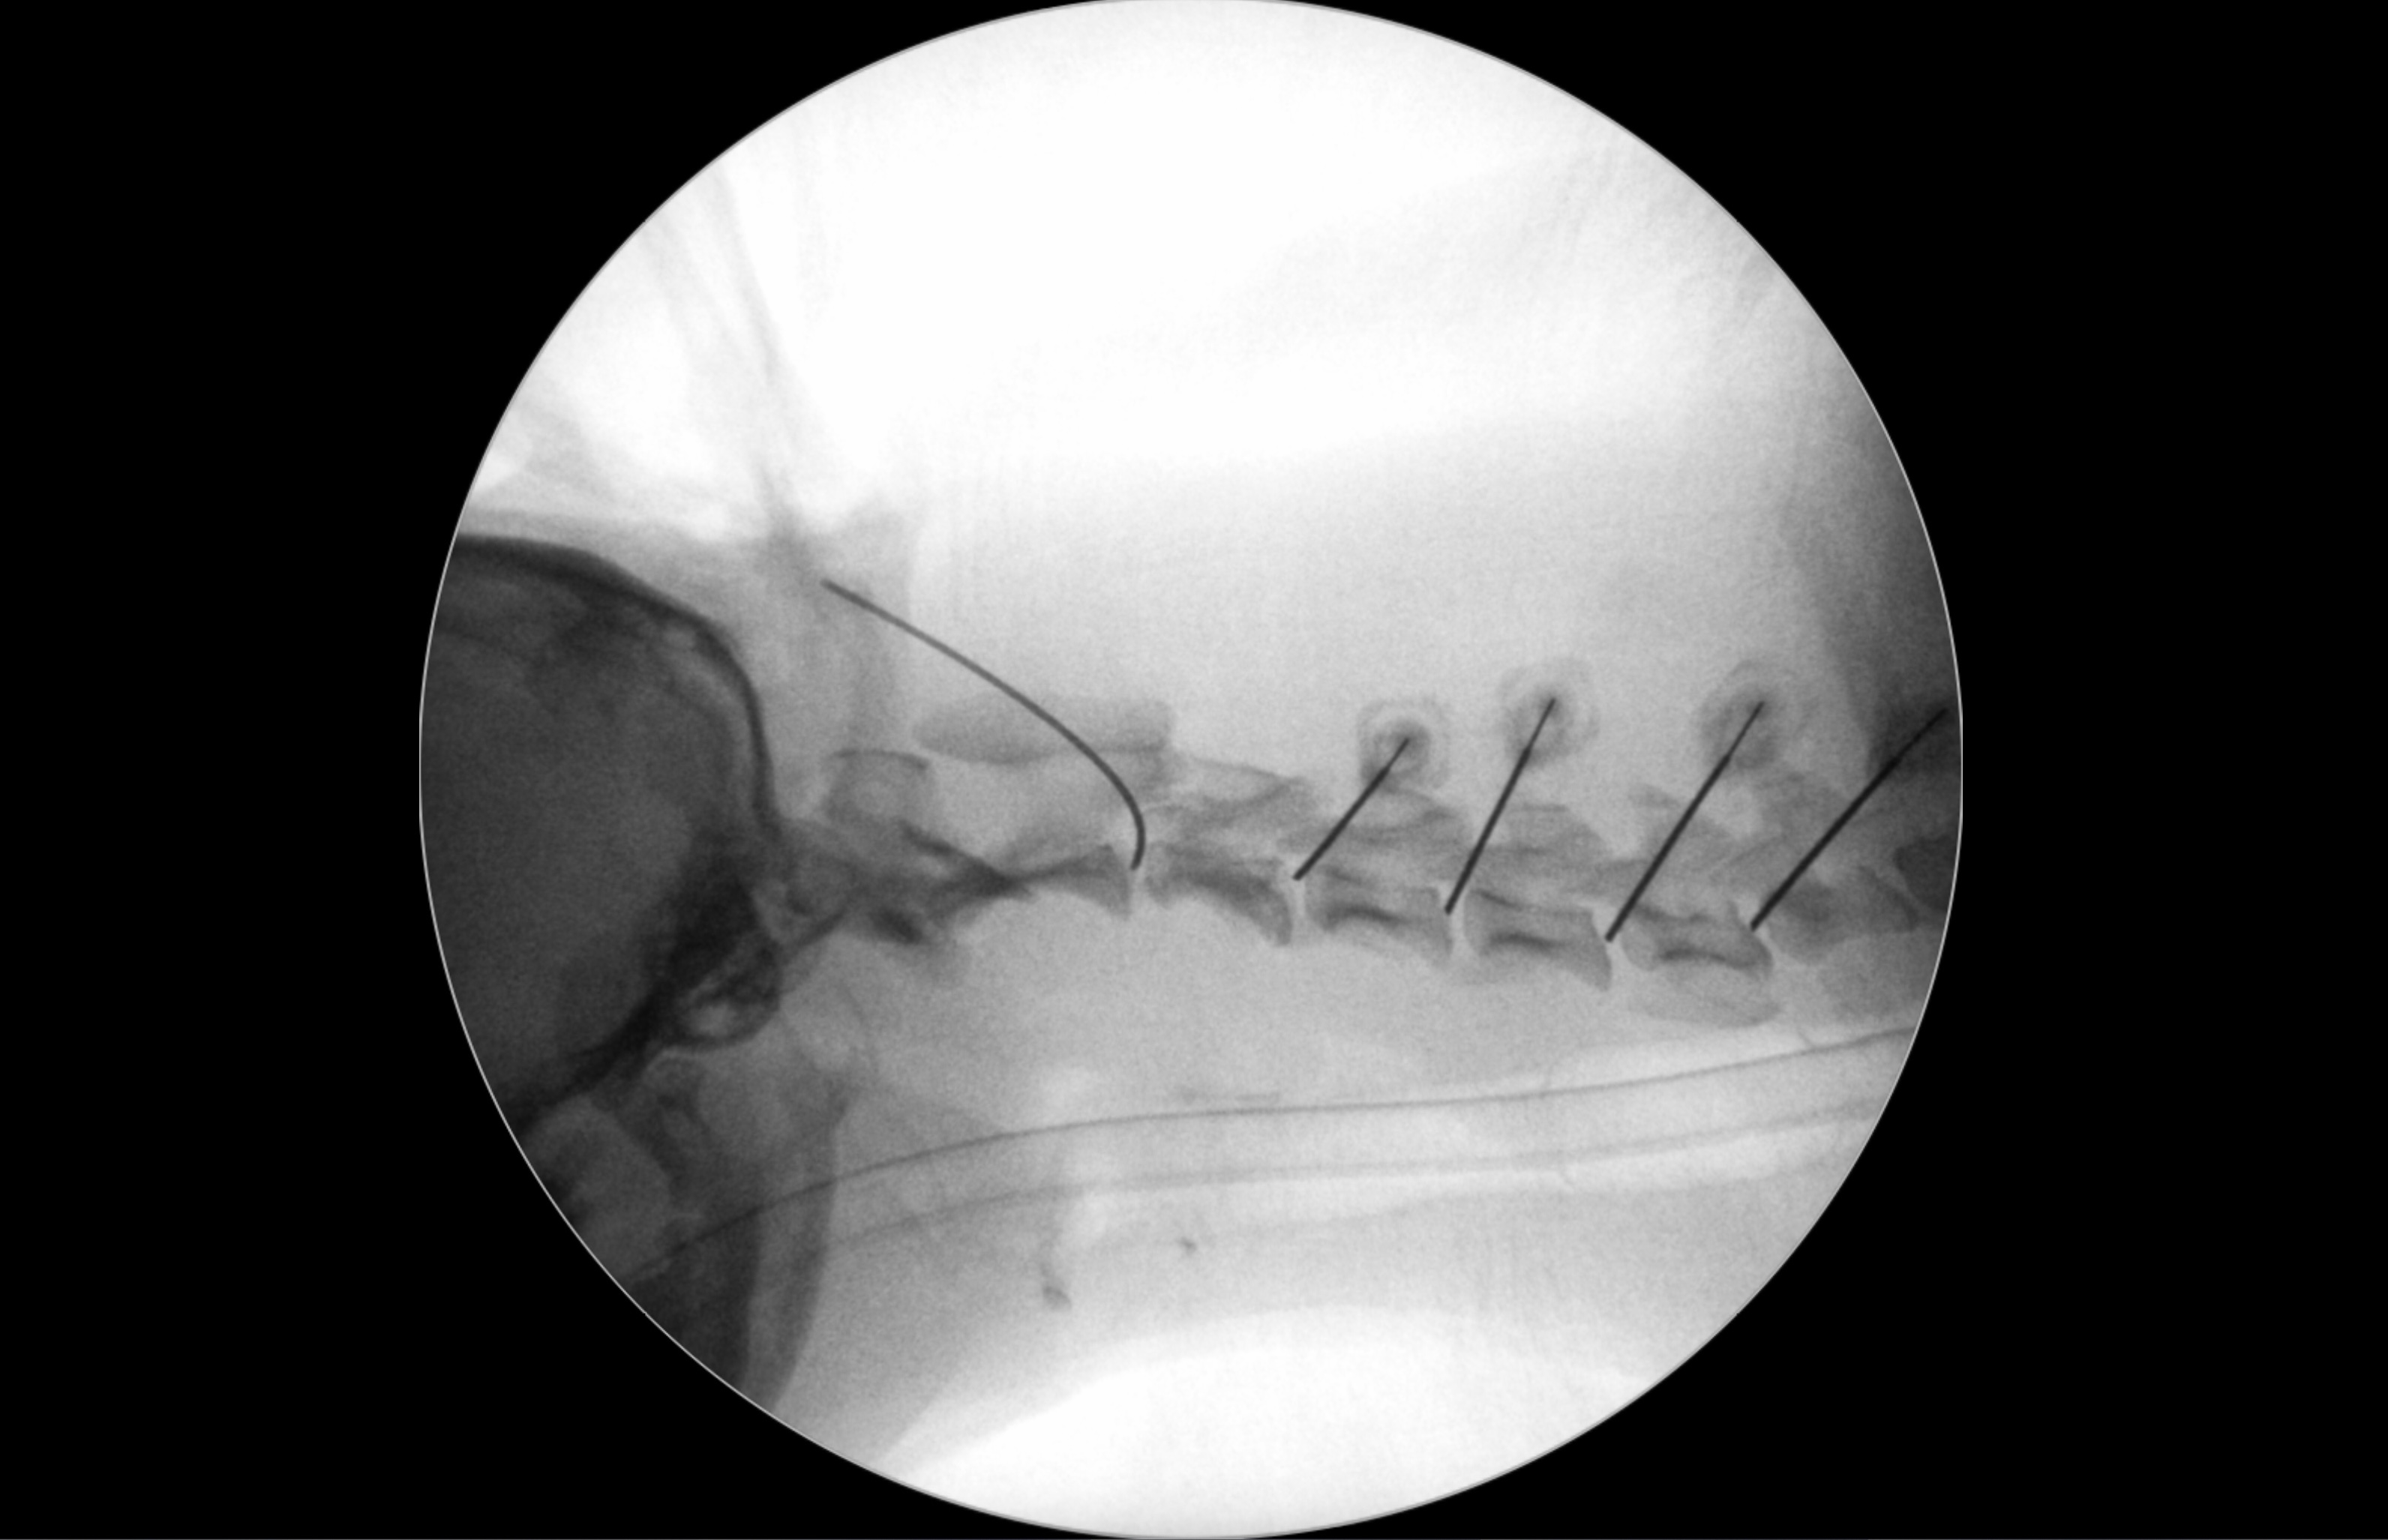

院内においても右前肢の挙上が認められ、単純X線画像検査を実施したところ、右側の橈骨遠位成長板領域の不透過性亢進、肘突起と上腕骨顆の間隙が広がっている所見が認められたため、橈骨遠位成長板早期閉鎖が疑われました。

前腕の側面像と頭尾側像 (黄丸と黄矢印:成長板の不透過性亢進 赤矢印:上腕骨顆と肘突起の間隙)